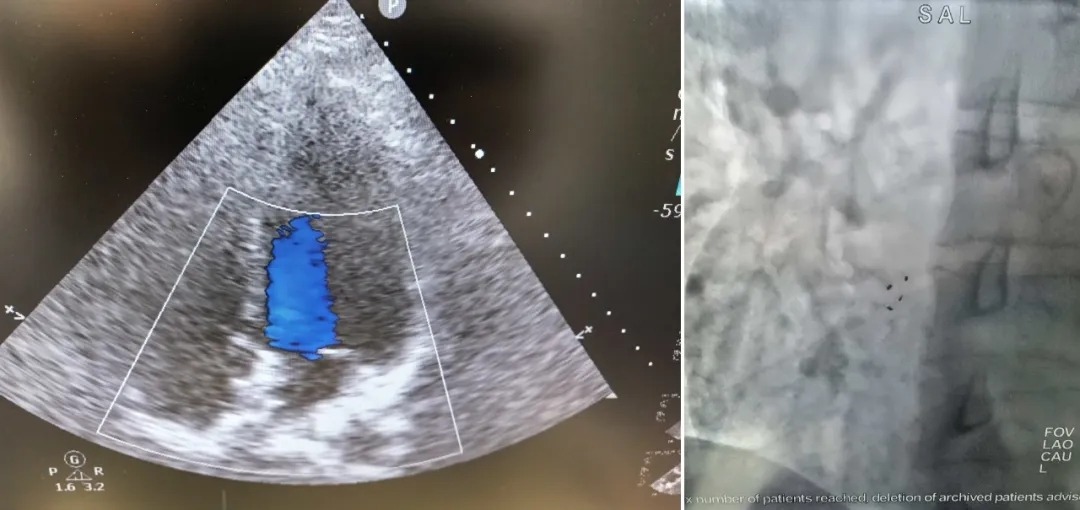

面对疑点,吴冠吉团队决定从可能引起“反常栓塞”的心脏结构入手。右心声学造影(发泡实验) 结果显示,患者心脏存在大量(III级)的右向左分流,强烈提示心脏内部存在异常通道。随后的 “金标准”检查——经食道超声心动图清晰显示,导致分流的正是卵圆孔未闭。这条心脏房间隔上的“小缝隙”,成为了微血栓进入脑动脉的潜在路径,解开了年轻患者出现脑梗死病灶的谜团。